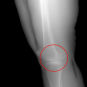

In this section, we provide qualitative and quantitative results of the two proposed diffusion-based methods and compare them with the baseline U-Net model. The first column of Fig. 3 showcases six randomly selected conditions: (a0)-(c0) show contour segmentations, and (d0)-(f0) denote segmentations containing contour and bones. In Fig. 3 (a1)-(f1), the images generated by U-Net contain blurred fine details in locations where bones overlap, despite maintaining the given shape, as highlighted by the red circle. In contrast, the results from CSM appear more realistic than the U-Net. However, their quality decreases with introduced constraints, as indicated by the red arrow in Fig. 3 (d2) and (f2). The results from CTM not only achieve nearly the same level of fineness as the labels but also provide reasonable results with respect to the given conditions as illustrated in the fourth column.

Table I summarizes the quantitative results averaged across all testing data. The evaluation metrics include mean absolute error (MAE) and peak signal-to-noise ratio (PSNR). We observed that CTM performs substantially better than U-Net and CSM under both segmentation-based conditions, and CSM performs worse than the U-Net.

Unlike the U-Net which learns a mapping function between input and output, the diffusion models can implicitly capture the underlying data distribution from the training data and then sample it, preventing the loss of fine details on the pixel level. However, in CSM, conditions are incorporated only at the first sampling step while being perturbed, which results in imprecise conditional information. Instead, CTM provides an estimated score function of the conditional distribution for each sampling step, accommodating both reliability and realism. Nonetheless, presently generated X-ray images only encompass independent 2D conditional information, which may introduce geometric inconsistencies between a set of projections. Future research will focus on modeling 3D probabilistic distributions with the provided 2D conditions to enable CT reconstruction from the generated projections. In addition, clinical datasets will also be incorporated.